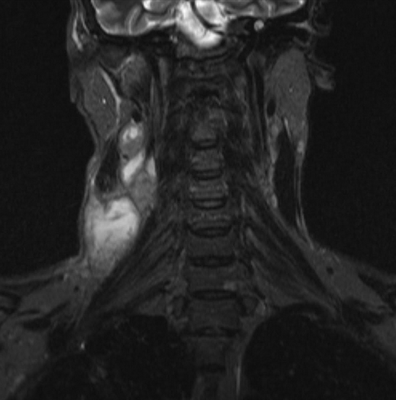

МРТ мягких тканей шеи

МРТ мягких тканей шеи назначают при наличии следующих симптомов:

дисфункция слюнных желез;

нарушения мозгового кровообращения;

признаки заболеваний щитовидной железы;

гипертония неясной этиологии и пр.